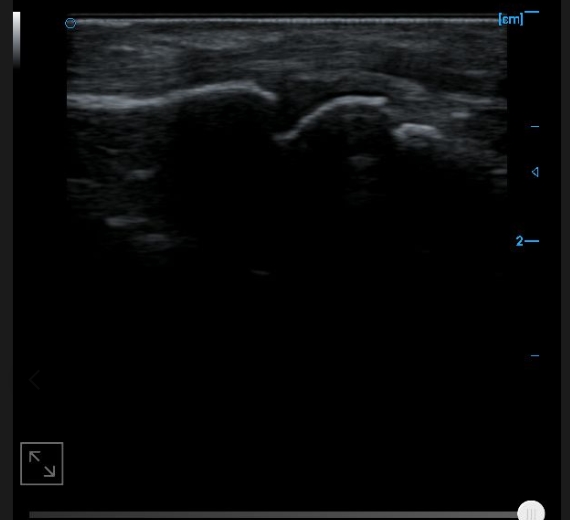

B-image of quadriceps tendon